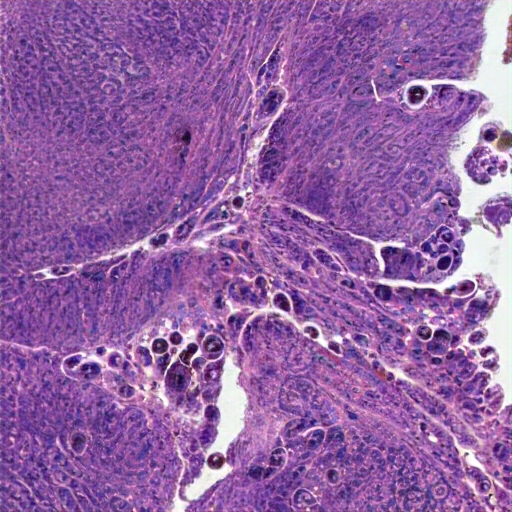

The colon tissue image exhibits glandular alterations with crowded, irregularly shaped glands lined by pleomorphic, hyperchromatic columnar epithelial cells, suggesting dysplasia. Varied gus-to-back gland ratio and visible nucleoli are observed. Inflammation, scant stroma, minimal inflammation between epithelial cells, and architectural distortion, indicate a possible neoplastic process. No invasive growth or deep invasion is seen, aligning with a diagnosis of a tubular adenomatous polyp, with possible high-to-mid dysplastic tumor growth. The stroma is moderately cellular. Findings indicate mild regenerative changes without high-grade dysplasia, but if into are not adenomas or adenomarcinoma. The glands vary in volume, however, shows architectural distortion, secretion of left-sided eosinophilic secretions, suggestive of a low-grade malignancy.